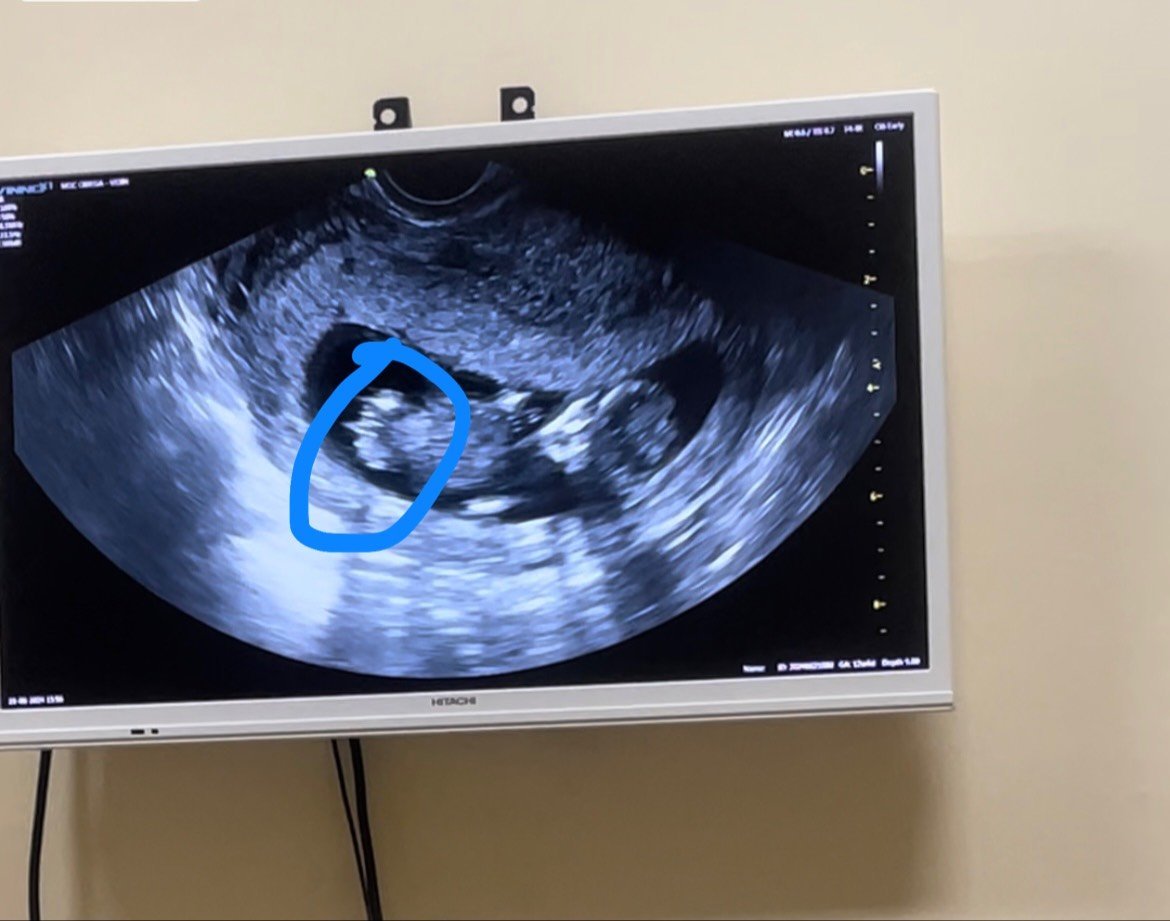

Здравейте ,прекрасни🌸 да се отпиша и аз ,днес мина мф и всичко е наррез,според лекаря много голяма вероятността да е момче💙 но ме гложди отвътре,тъй като не каза на 100% .Ще прикача снимка според вас момче ли е ?